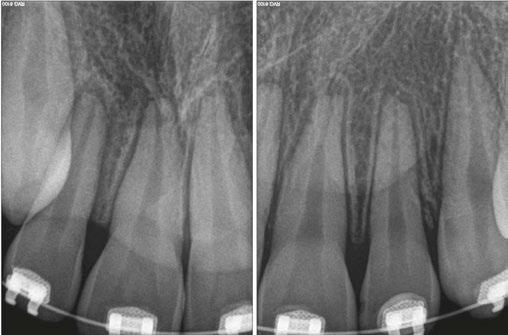

Luckily, the young boy was undergoing orthodontic treatment so the avulsed teeth remained in the oral cavity. As you can see from the clinical photograph in Figure 1, teeth Nos. 8, 9, and 10 would not have remained in the mouth if the orthodontic wire was not in place.

Two days after treatment, the patient was seen in my practice after the teeth were splinted back in place by the orthodontist. Figures 2A-2B are the preoperative radiographs after the teeth were reimplanted.

One can already appreciate the inflammatory resorption that is occurring at the apices of teeth Nos. 9 and 10. These images were taken just two days after the trauma.

There was some sealer extrusion at the apex of these teeth (Figure 7), especially 10, but this was due to the inflammatory resorption occurring at the apex as a result of the trauma, which started to eat away the apical stop. I am confident that, over time, this sealer will resorb away, and this extrusion should not impede the healing at all. Figure 8 is the final outcome of the case.